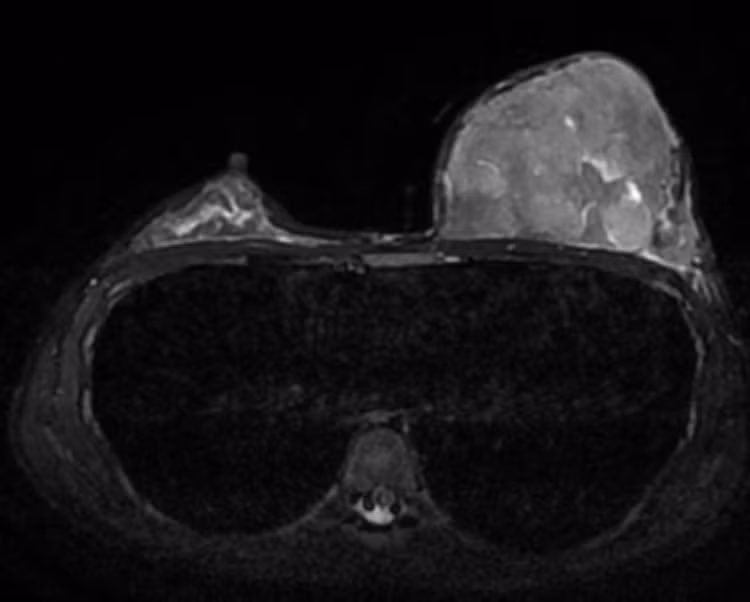

| Hình ảnh MRI cho thấy vú trái phát triển kích cỡ to bất thường so với vú phải. |

Kết quả xét nghiệm cho thấy chỉ số hormone Prolactin (một loại hormone liên quan tới tuyến vú) tăng cao. Chụp X-quang vú phát hiện phì đại, tăng đậm độ lan toả tuyến vú trái. Quá trình siêu âm vú, bác sĩ nhận thấy hình ảnh tăng âm, tăng kích thước tuyến vú trái. Chụp MRI tuyến vú thấy khối u lớn nhu mô vú trái, không xân lấn thành ngực, kích thước 124 x 87 x 64 mm.